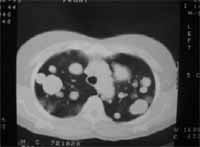

Figura 9. Enfermedad pulmonar metastásica.

Figura 11. Enfermedad pulmonar metastásica.